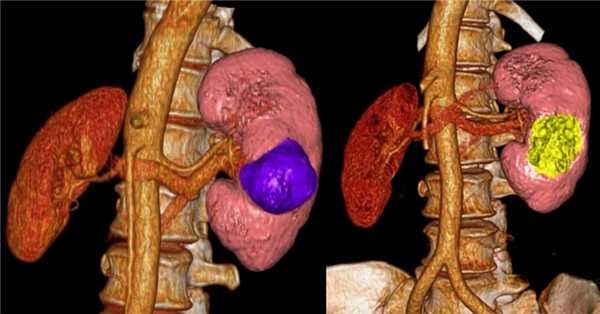

3D-реконструкции опухоли Вильмса пациентов детского отделения НМИЦ онкологии им. Н.Н. Петрова